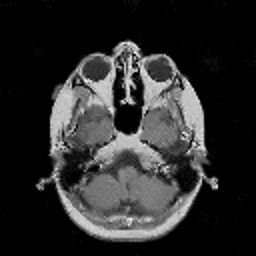

VII-C Experiments with real-life data

Reconstruction of real-life MRI images has been the next step in our comparative study. To this end, the data set of [19] have been used herein. The data were obtained at the University Hospital of Ghent and it is publicly available at http://telin.ugent.be/~sanja/Sanja_files/Software/MRIprogram.zip. The data contains a sagittal and an axial scan of a human brain, which are shown in Fig. 10 and Fig. 11, respectively.

The reconstruction results obtained for each of the tested images using the proposed and reference methods are shown in Subplots (b)-(f) of Fig. 10 and Fig. 11, respectively. From these figures, it can be seen that the proposed algorithms result in higher-contrast reconstructions of better visual clarity as compared to the reference approaches. The difference is particularly evident for the case of Fig. 11, where the proposed algorithms result in less noisy images, while exhibiting higher effective resolution and contrast.